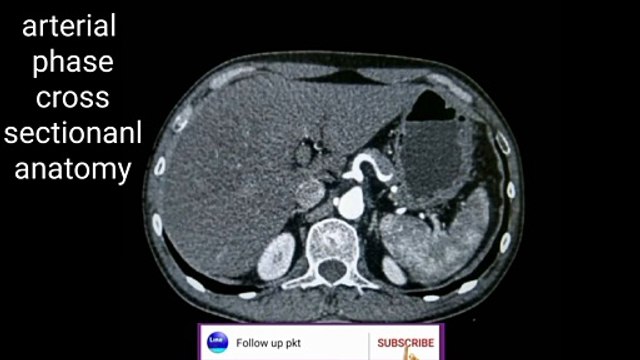

Arterial phase cross-sectional anatomy

Uploaded: February 7, 2022 Views: 0